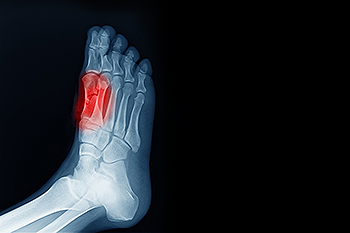

Most cases of gout are easily diagnosed by a podiatrist’s assessment of the various symptoms. Defined tests can also be performed. A blood test to detect elevated levels of uric acid is often used as well as an x-ray to diagnose visible and chronic gout.